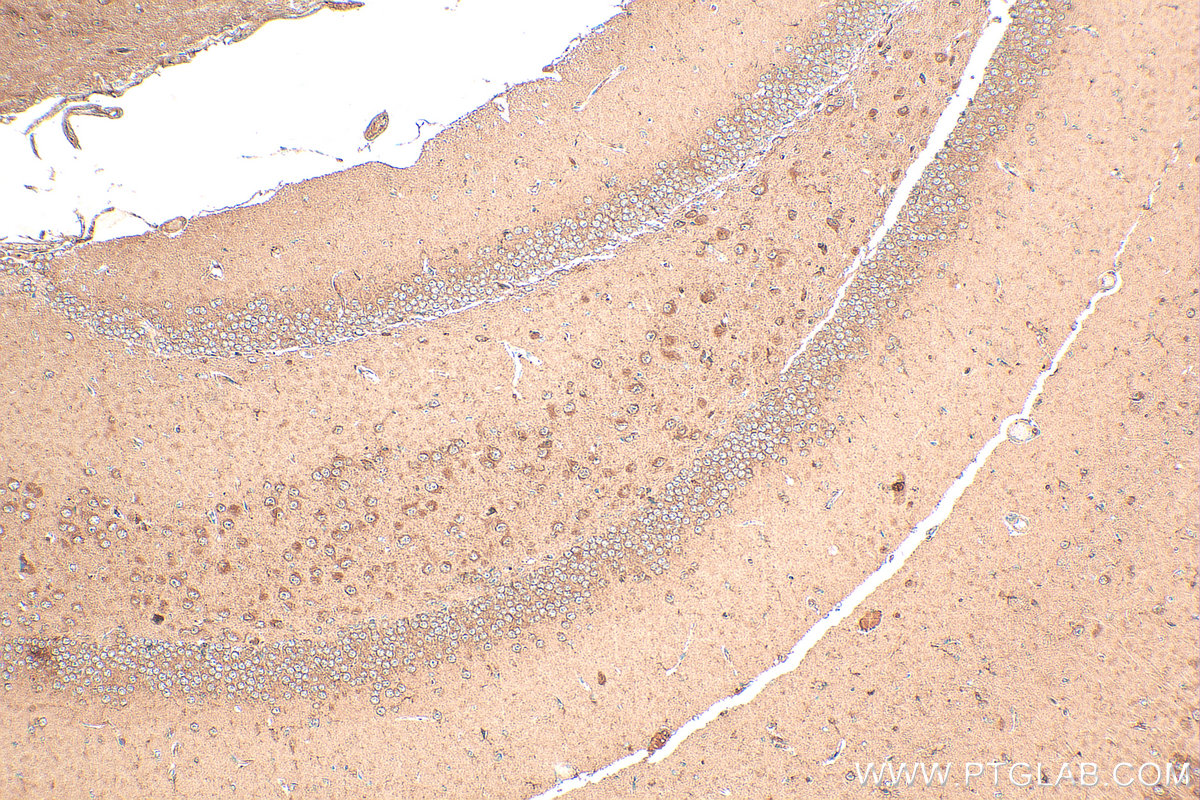

| Positive IHC detected in | mouse brain tissue Note: suggested antigen retrieval with TE buffer pH 9.0; (*) Alternatively, antigen retrieval may be performed with citrate buffer pH 6.0 |

| Immunohistochemistry (IHC) | IHC : 1:50-1:500 |